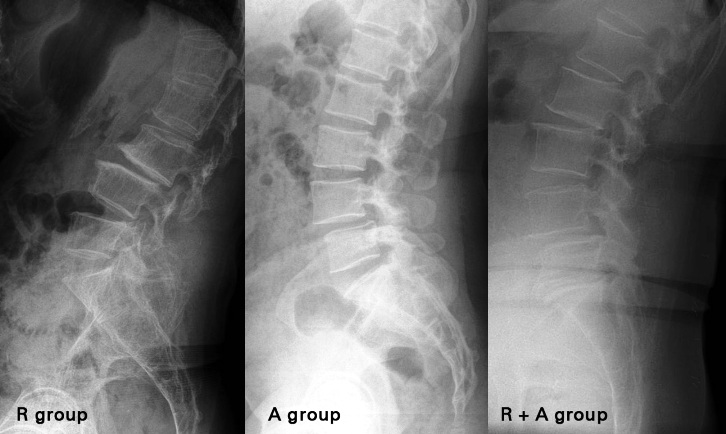

Retrolisthesis is a medical condition in which vertebrae in the spine are displaced from their original position. Vertebrae move forward in many cases and backward movement is less common but occurs with considerable frequency in people with degenerative disorders. It occurs in the soft disc that separates and cushions the vertebrae. It is of three types:

Retrolisthesis is a term used to define an acute spine condition in which the backward slippage of one vertebra onto the other vertebra immediately below it takes place. Vertebrae are the bones that make up the spinal column and are separated from each other by cushioning intervertebral discs. Hence, Retrolisthesis is a posterior displacement of the vertebral body with respect to the adjacent vertebrae to a degree less than a luxation or dislocation. Retrolisthesis is seen in the cervical spine and lumbar region and also in the thoracic region.

Retrolisthesis is a degenerative or congenital condition in which the vertebra of spine gets displaced and moves backward onto the vertebra lying below it. Retrolisthesis acts as a compensatory mechanism for moving the gravity axis posteriorly for the sagittal imbalance in lumbar spine under low pelvic incidence and insufficient intra-spinal compensation .In most cases of vertebral slippage, it will involve a forward movement of an upper vertebra which will slip towards the chest.